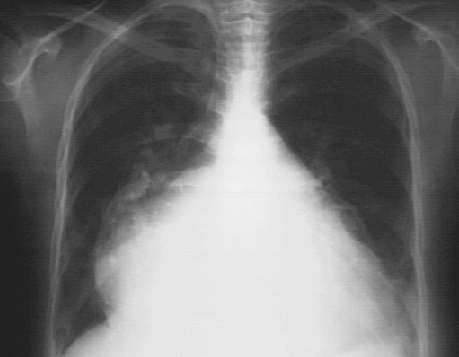

PA

These chest X rays show marked left atrial enlargement.

In this PA view the marked left atrial enlargement is demonstrated by the atrial appendage along the left heart border and is so massive that it also comprises the right heart border. Such a giant left atrium may be seen in severe chronic mitral regurgitation.